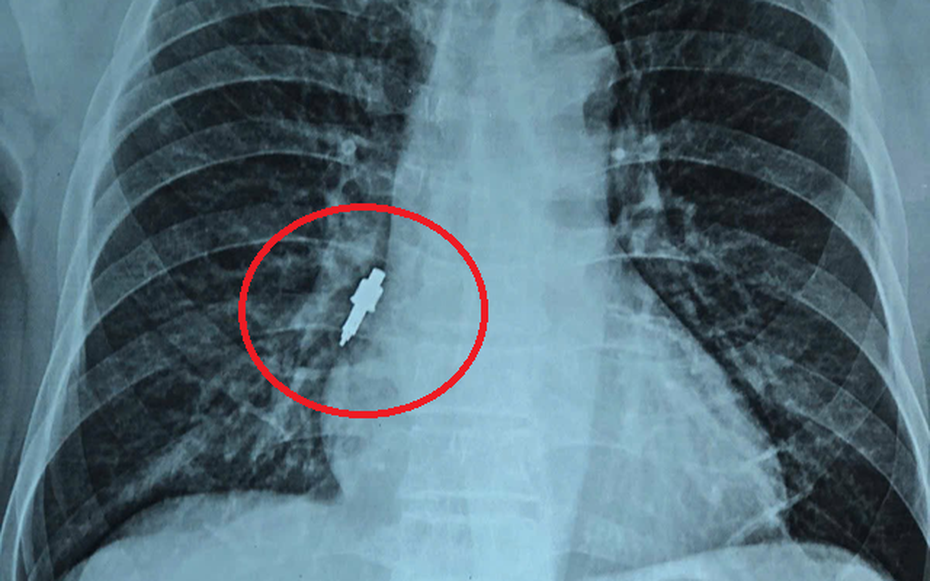

Dị vật trong phế quản của bệnh nhân. Ảnh: BVCC.

Sau đó, bệnh nhân xuất hiện ho nhẹ kéo dài. Khi cơn ho trở nên dữ dội, gia đình đưa ông đi khám. Kết quả chụp X-quang cho thấy có dị vật nằm trong phế quản phải nên bệnh nhân được chuyển gấp tới Bệnh viện Hữu Nghị.

Tại đây, các bác sĩ quyết định tiến hành nội soi phế quản cấp cứu. Dị vật được xác định bằng inox, bề mặt trơn, đường kính 1cm, dài 2,5cm và mắc sâu vào phế quản phải, kìm sinh thiết thông thường không thể gắp ra.

Dị vật như chiếc mũi khoan trong đường hô hấp của bệnh nhân được lấy ra.